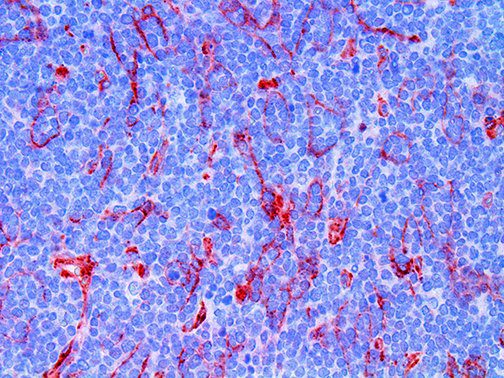

It is the ICU physician who is most likely to witness one of the deadliest manifestations of the abnormal immunological response, the cytokine storm syndrome (CSS). This response is also referred to by some as the cytokine release syndrome (CRS). CSS is characterized by continuous activation and expansion of macrophage and lymphocyte populations, which secrete large amounts of cytokines, causing the cytokine storm. This massive cytokine release is akin to hemophagocytic lymphohistiocytosis (HLH) disease, a syndrome characterized by initial unchecked and persistent activation of cytotoxic T lymphocytes and NK cells.

Clinical and laboratory manifestations of HLH include fever, enlarged liver and/or spleen, neurologic dysfunction, coagulopathy, liver dysfunction, cytopenias (i.e., low levels of erythrocytes, leukocytes, and/or platelets), hypertriglyceridemia, hyperferritinemia, hemophagocytosis, and eventually diminished NK cell activity as the immune system becomes progressively paralyzed. HLH can be familial (primary HLH) or secondary to another disease process (sHLH), such as rheumatic disease, in which it is referred to as macrophage activation syndrome (MAS, characterized by elevated ferritin).